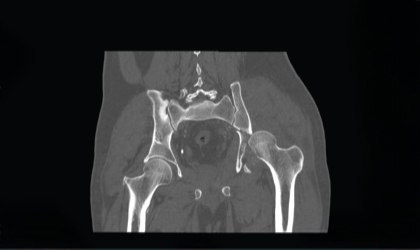

We performed fixation of the fracture and, due to the compromised head of the femur, proceeded with a hip replacement during the same surgery. This complex procedure required precise alignment and implant positioning.

Post-surgery, the patient underwent structured rehabilitation. Within a short time, he regained mobility and is now back on his feet, walking comfortably.

The patient has recovered well following this highly complex procedure. He is now mobile and back to his regular activities, with restored hip function and no pain.